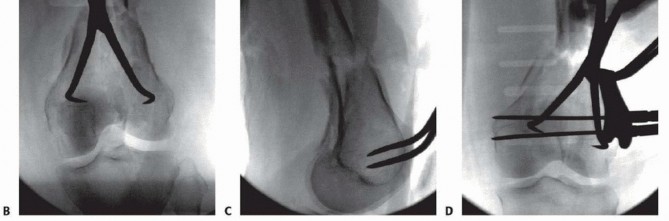

TECH FIG 11 • Patient with closed distal femur fracture (also shown in FIG 5G,H and 6C-E). A. Limited lateral incision, with the tibial tubercle marked. B. Skin incision showing the iliotibial band. C. Incision of the iliotibial band. D. Exposure of the lateral aspect of the femur. 487 ### Stabilizing the Articular Surface For nondisplaced type C1 or C2 fractures, the first priority is to stabilize the articular surface. Visualization of the joint may be accomplished with placement of a blunt Hohmann retractor (or similar Z retractor) ( TECH FIG 12A).

---

### TECH FIG 12 • A. Visualization of the joint for articular reduction. B. C-arm image of reduction forceps holding the intercondylar split reduced. C,D. Clinical photographs with forceps followed by guidewires for screw placement. E,F. Lateral views showing pins and wires outside the zone for either plate application or intramedullary nail. The anterior and posterior placement of the pins is seen. (continued) A reduction forceps is placed anteriorly to hold the reduction ( TECH FIG 12B). Temporary Kirschner wires or guidewires from a cannulated system can be placed for additional stability ( TECH FIG 12C,D). All clamps, Kirschner wires, or guidewires should be placed outside the zone of plate application ( TECH FIG 12E,F). 488

--- - TECH FIG 12 • (continued) G. Definitive fixation of the condyles with 4.5-mm partially threaded cannulated screws. Definitive fixation of the condyles should be performed (see technique description earlier) ( TECH FIG 12G). ### Reduction of the Distal Segment and Plate Placement Reduction of the distal segment to the shaft can be performed using temporary Steinmann pins ( TECH FIG 13). The plate can now be applied in a submuscular fashion (see Placement of the Plate section earlier). ### Wound Closure Final radiographs are taken in the operating room ( TECH FIG 14). Standard wound closure is undertaken, as described in the previous section. ### Retrograde Nailing(FIG 10A-F) Refer to Chapter 43 on retrograde nailing of the femur.